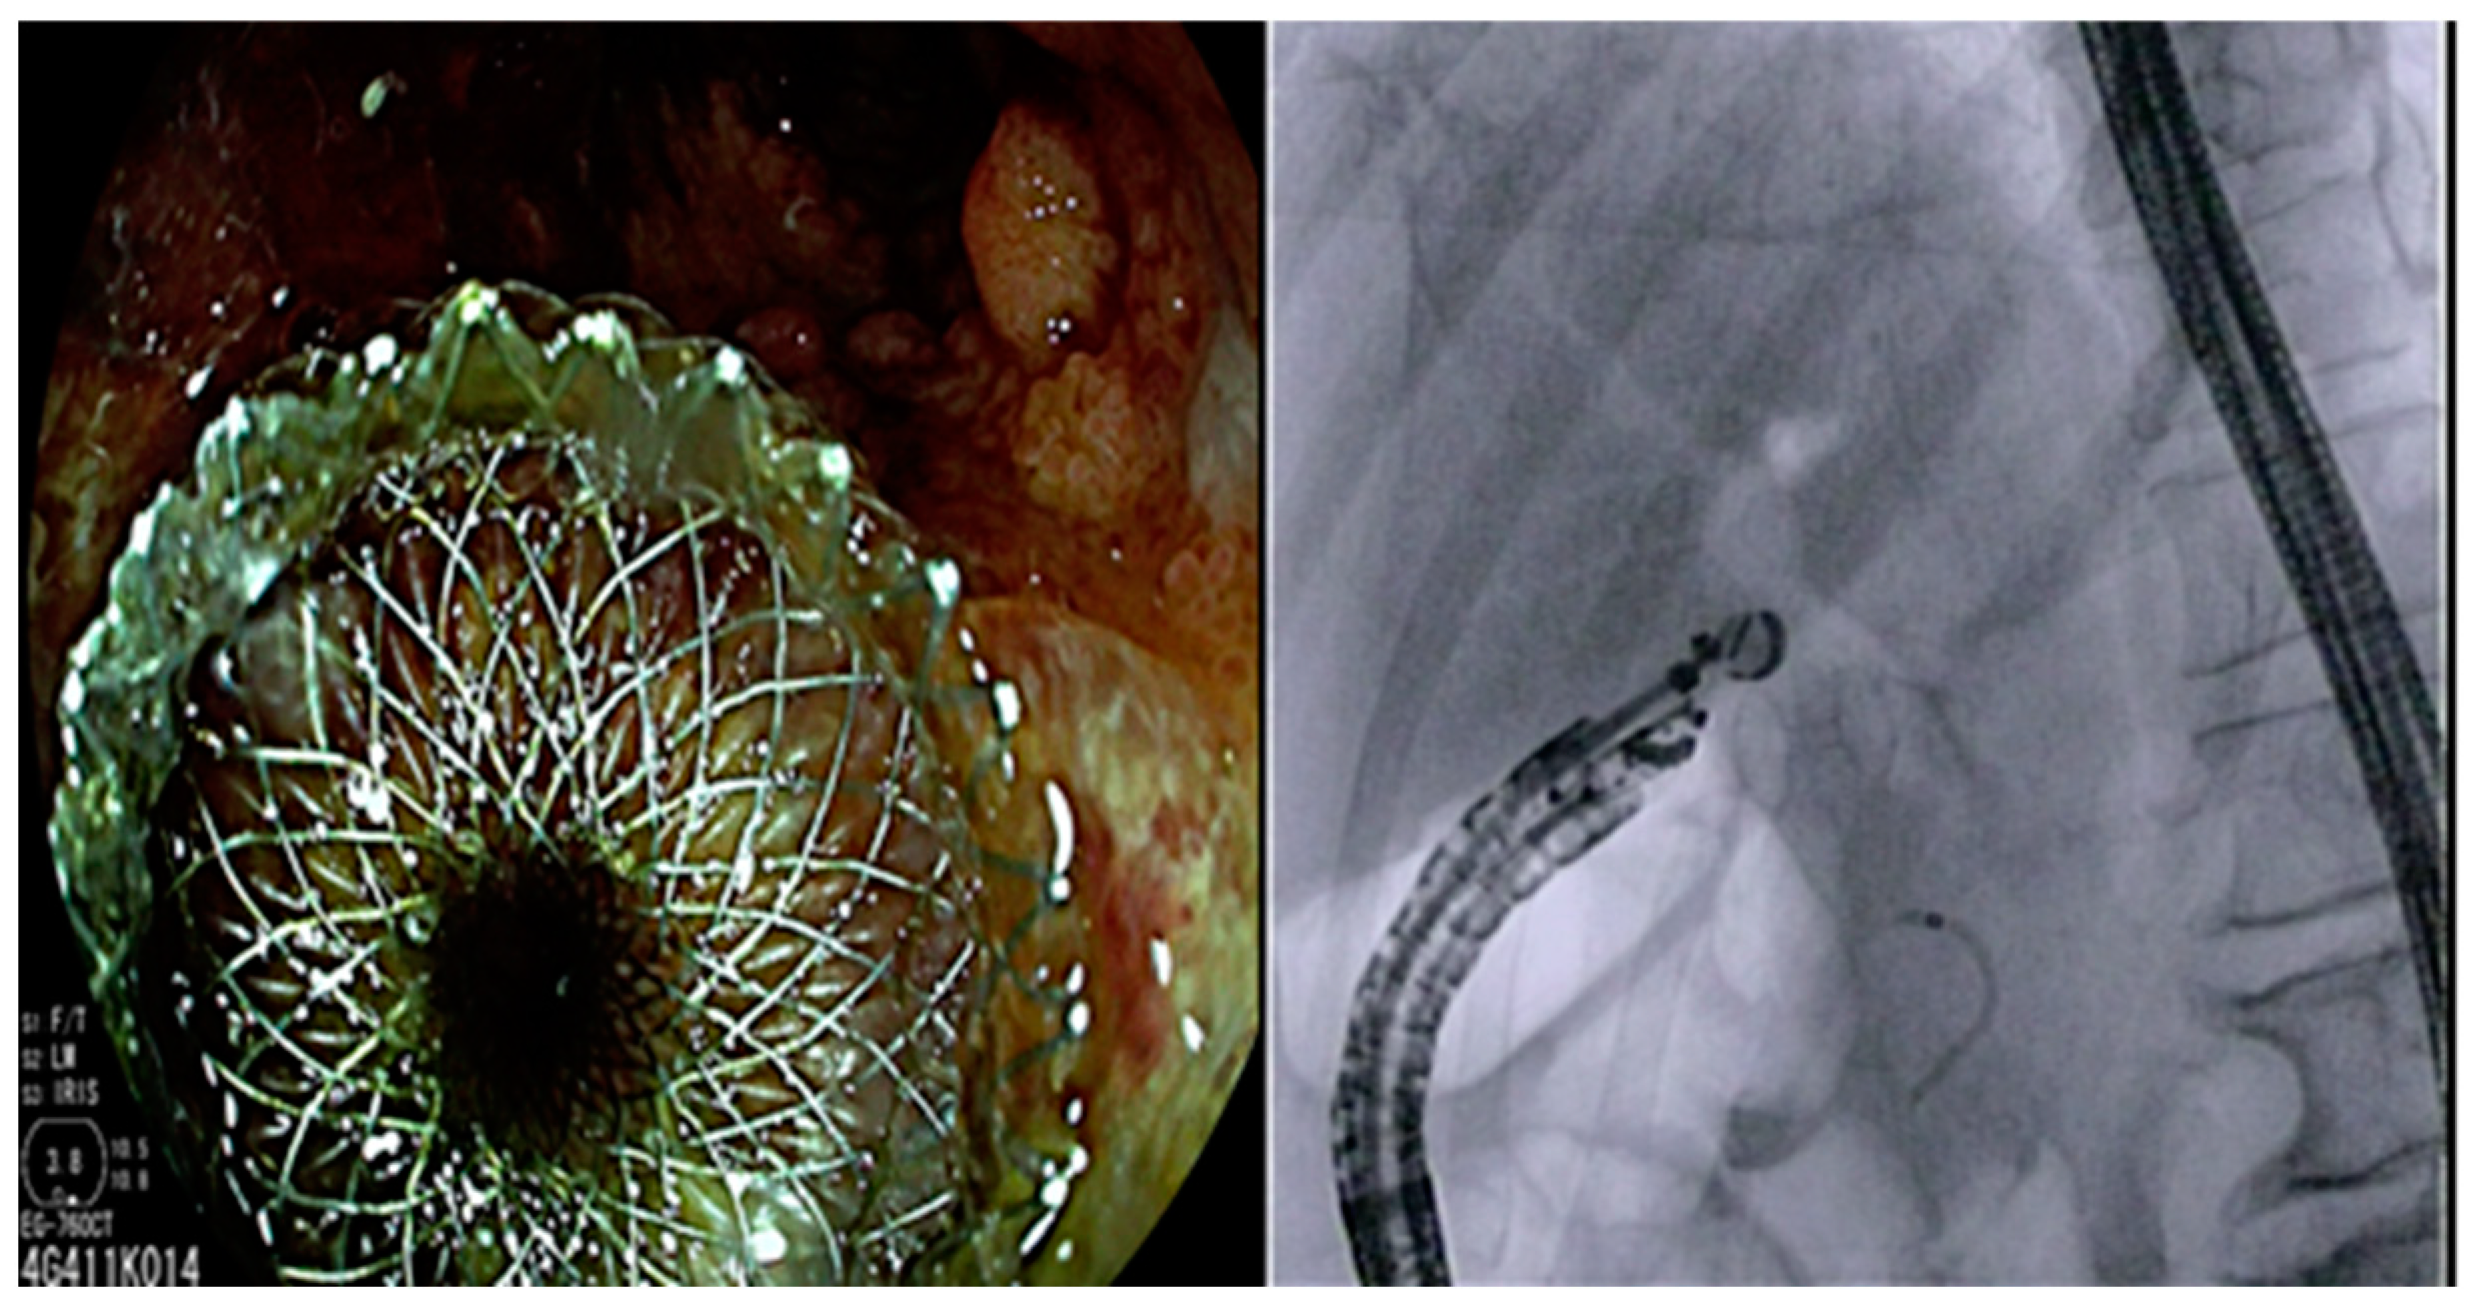

Figure 1. Endoscopic and fluoroscopic image obtained after electrocautery lumen-apposing metal stent (EC-LAMS) deployment in the duodenal lumen.

The procedure is generally performed in an endoscopic room with fluoroscopic equipment and with the patient under conscious sedation or general anesthesia. First, a linear array echoendoscope is advanced until the second duodenal portion. The duodenal bulb is commonly the preferred site to identify the target, namely the CBD. A good diagnostic EUS, including the use of Color Doppler, should always be performed to locate vessels and other structures surrounding the intended puncture site. In the case of EUS-CDS, a dilated CBD (≥15 mm) and a short distance (≤10 mm) between the CBD and the duodenal wall are prerequisites for the correct deployment of the stent. A unique feature of LAMS is their bi-flanged shape which gives them the ability to approximate two structures, thereby minimizing the potential risk of leak and dislodgment. Moreover, thanks to their wider lumen, the stents may serve as an access to structures adjacent to the gastrointestinal tract for performing various interventions if required. Over the years, the design of these innovative stents has evolved. Current devices are made of nitinol wire and are fully covered with a silicone membrane which avoids the risk of tissue ingrowth. Nowadays, two types of LAMS are most popular worldwide: the AXIOS stent (Boston Scientific Corporation, Natick, MA, USA) and the NAGI or SPAXUS stents (Taewoong Medical, Gyeonggi-do, South Korea). The deployment of the stent may be performed with the over-the-wire technique or the single-stage technique “freehand”. In the classic technique, the CBD is first punctured with a 19-gauge needle; the injection of contrast confirms the correct target and aspiration of bile can be performed to double check the placement. Then, a 0.025 or 0.035 inch guidewire is inserted into the CBD, and dilation of the fistula, using a cystotome or a dilation balloon, is performed to facilitate the insertion of the stent. The advent of electrocautery-enhanced LAMS (EC-LAMS) allowed a single-step procedure with direct passage of the catheter into the target structure without prior needle access and tract dilation, avoiding device exchange and reducing the procedure time and complexity. The Axios stent was the first electrocautery-enhanced delivery system (EC-LAMS, Hot-Axios, Boston Scientific Corporation, Natick, MA, USA) released into the market, leading to its widespread adoption. Recently, the EC-LAMS version of Spaxus (Hot-Spaxus, Taewoong Medical, Gyeonggi-do, South Korea) has been released into the market and approved for pancreatic fluid collection and GBD [18]. Specifically, for the Hot-Axios system, the EC-LAMS catheter is inserted into the working channel of the echoendoscope and secured to the inlet port of the working channel. The tip of the catheter is positioned tangentially to the CBD. Subsequently, the delivery system is connected to an electrocautery generator and the catheter is introduced into the duct with the application of cautery. When the catheter is fully inside the target structure, the first flange of the stent is deployed, and the confirmation of the correct position is given in real time by ultrasonography. Then, the catheter is slightly withdrawn until the first flange is in contact with the CBD wall. At this point there are two techniques for the release of the second flange. In the first technique, the delivery system is manipulated until a black mark becomes visible at the point where the catheter enters the intestinal mucosa. Then, the system is gently pulled upward to properly position and deploy the proximal flange of the LAMS under endoscopic observation. Alternatively, the intra-channel stent release technique can be utilized, which is considered safer due to its reduced risk of stent dislodgement. In this technique, the stent is inserted into the working channel of the echoendoscope and subsequently pushed out as the echoendoscope is gradually withdrawn (Figure 1) [19,20].